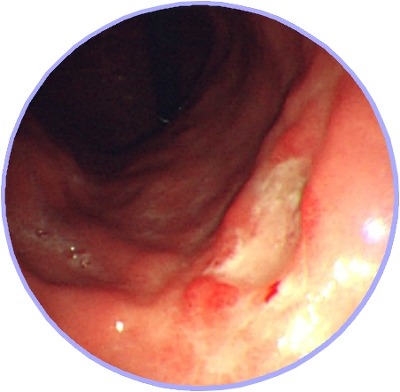

- 위암 초기증상 : 혈변

검은변 그리고 혈변 역시 위암 초기 증세를 의심가능한데 당연하고 변의 색만으로써 암을 예단해서는 어렵지만 위에서 말씀드린 초기증상과 또한 암이 진행되며 염증이 생겨 종양이 혈관을 압박하여 출혈을 유발하는 상황에 생길 수 있눈데 출혈량이 많아지면 혈액이 소화관을 통해 대변으로서 흘러 들어가 혈액이 대변으로써 흘러 들어가거나 대변이 검게 변하기 때문에 위암 초기증상을 의심해봐야 해요.